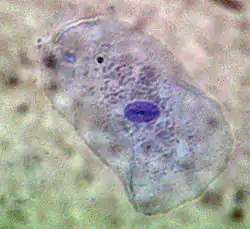

Photo of cultured mast cells at 100× stained with Tol Blue

One of the most outstanding results of his dissertation investigations was the discovery of a new cell type. Ehrlich discovered in the protoplasm of supposed plasma cells a granulate which could be made visible with the help of an alkaline dye. He thought this granulate was a sign of good nourishment, and accordingly named these cells mast cells, (from the German word for an animal-fattening feed, Mast). This focus on chemistry was unusual for a medical dissertation. In it, Ehrlich presented the entire spectrum of known staining techniques and the chemistry of the pigments employed. While he was at the Charité, Ehrlich elaborated upon the differentiation of white blood cells according to their different granules. A precondition was a dry specimen technique, which he also developed. A drop of blood placed between two glass slides and heated over a Bunsen burner fixed the blood cells while still allowing them to be stained. Ehrlich used both alkaline and acid dyes, and also created new "neutral" dyes. For the first time this made it possible to differentiate the lymphocytes among the leucocytes (white blood cells). By studying their granulation he could distinguish between nongranular lymphocytes, mono- and poly-nuclear leucocytes, eosinophil granulocytes and mast cells.